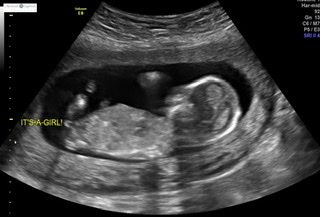

Hi! I had an elective ultrasound at 14 weeks and the tech was confident it is a girl based on both nub and potty shot. I swayed for a girl so praying she is right!! What do you think? P.s. sorry if these pictures are uploaded weird or doubles.. never done pictures before lol Attachment 42861Attachment 42862Attachment 42863Attachment 42862Attachment 42863Attachment 42864